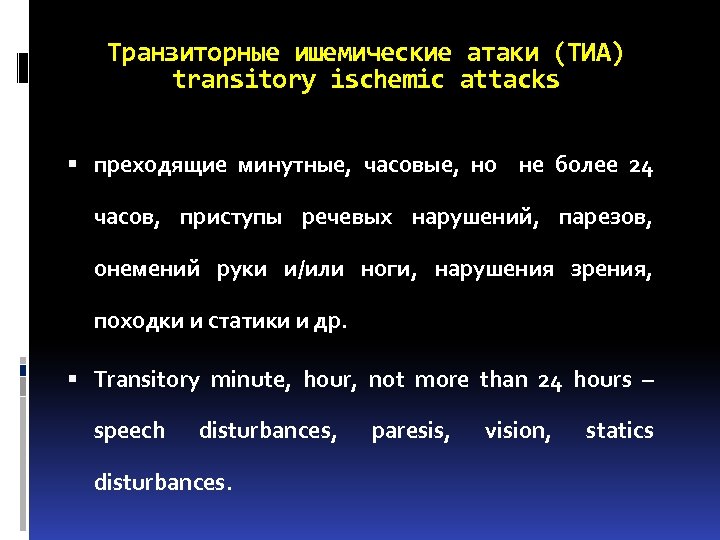

Транзиторные ишемические атаки (ТИА) transitory ischemic attacks преходящие минутные, часовые, но не более 24 часов, приступы речевых нарушений, парезов, онемений руки и/или ноги, нарушения зрения, походки и статики и др. Transitory minute, hour, not more than 24 hours – speech disturbances, disturbances. paresis, vision, statics

Транзиторные ишемические атаки (ТИА) transitory ischemic attacks преходящие минутные, часовые, но не более 24 часов, приступы речевых нарушений, парезов, онемений руки и/или ноги, нарушения зрения, походки и статики и др. Transitory minute, hour, not more than 24 hours – speech disturbances, disturbances. paresis, vision, statics